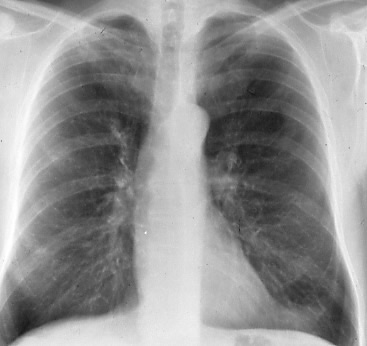

Fig. 3: Posterior-anterior radiographs showing (a) an extensive bronchogenic carcinoma in the right lung and (b) four months after initiation of chemotherapy, a complete remission, rT0.